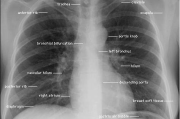

胸片全体曝光问题解析-医学影像质量控制与患者安全 在现代医学影像中,胸片是一种常见的检查方式,它可以帮助医生诊断多种胸部疾病。胸片全体曝光的问题在医疗实践中引起了广泛关注,这不仅关系到患者的健康安全,也关系到影... 服饰 admin 19 2026-01-21